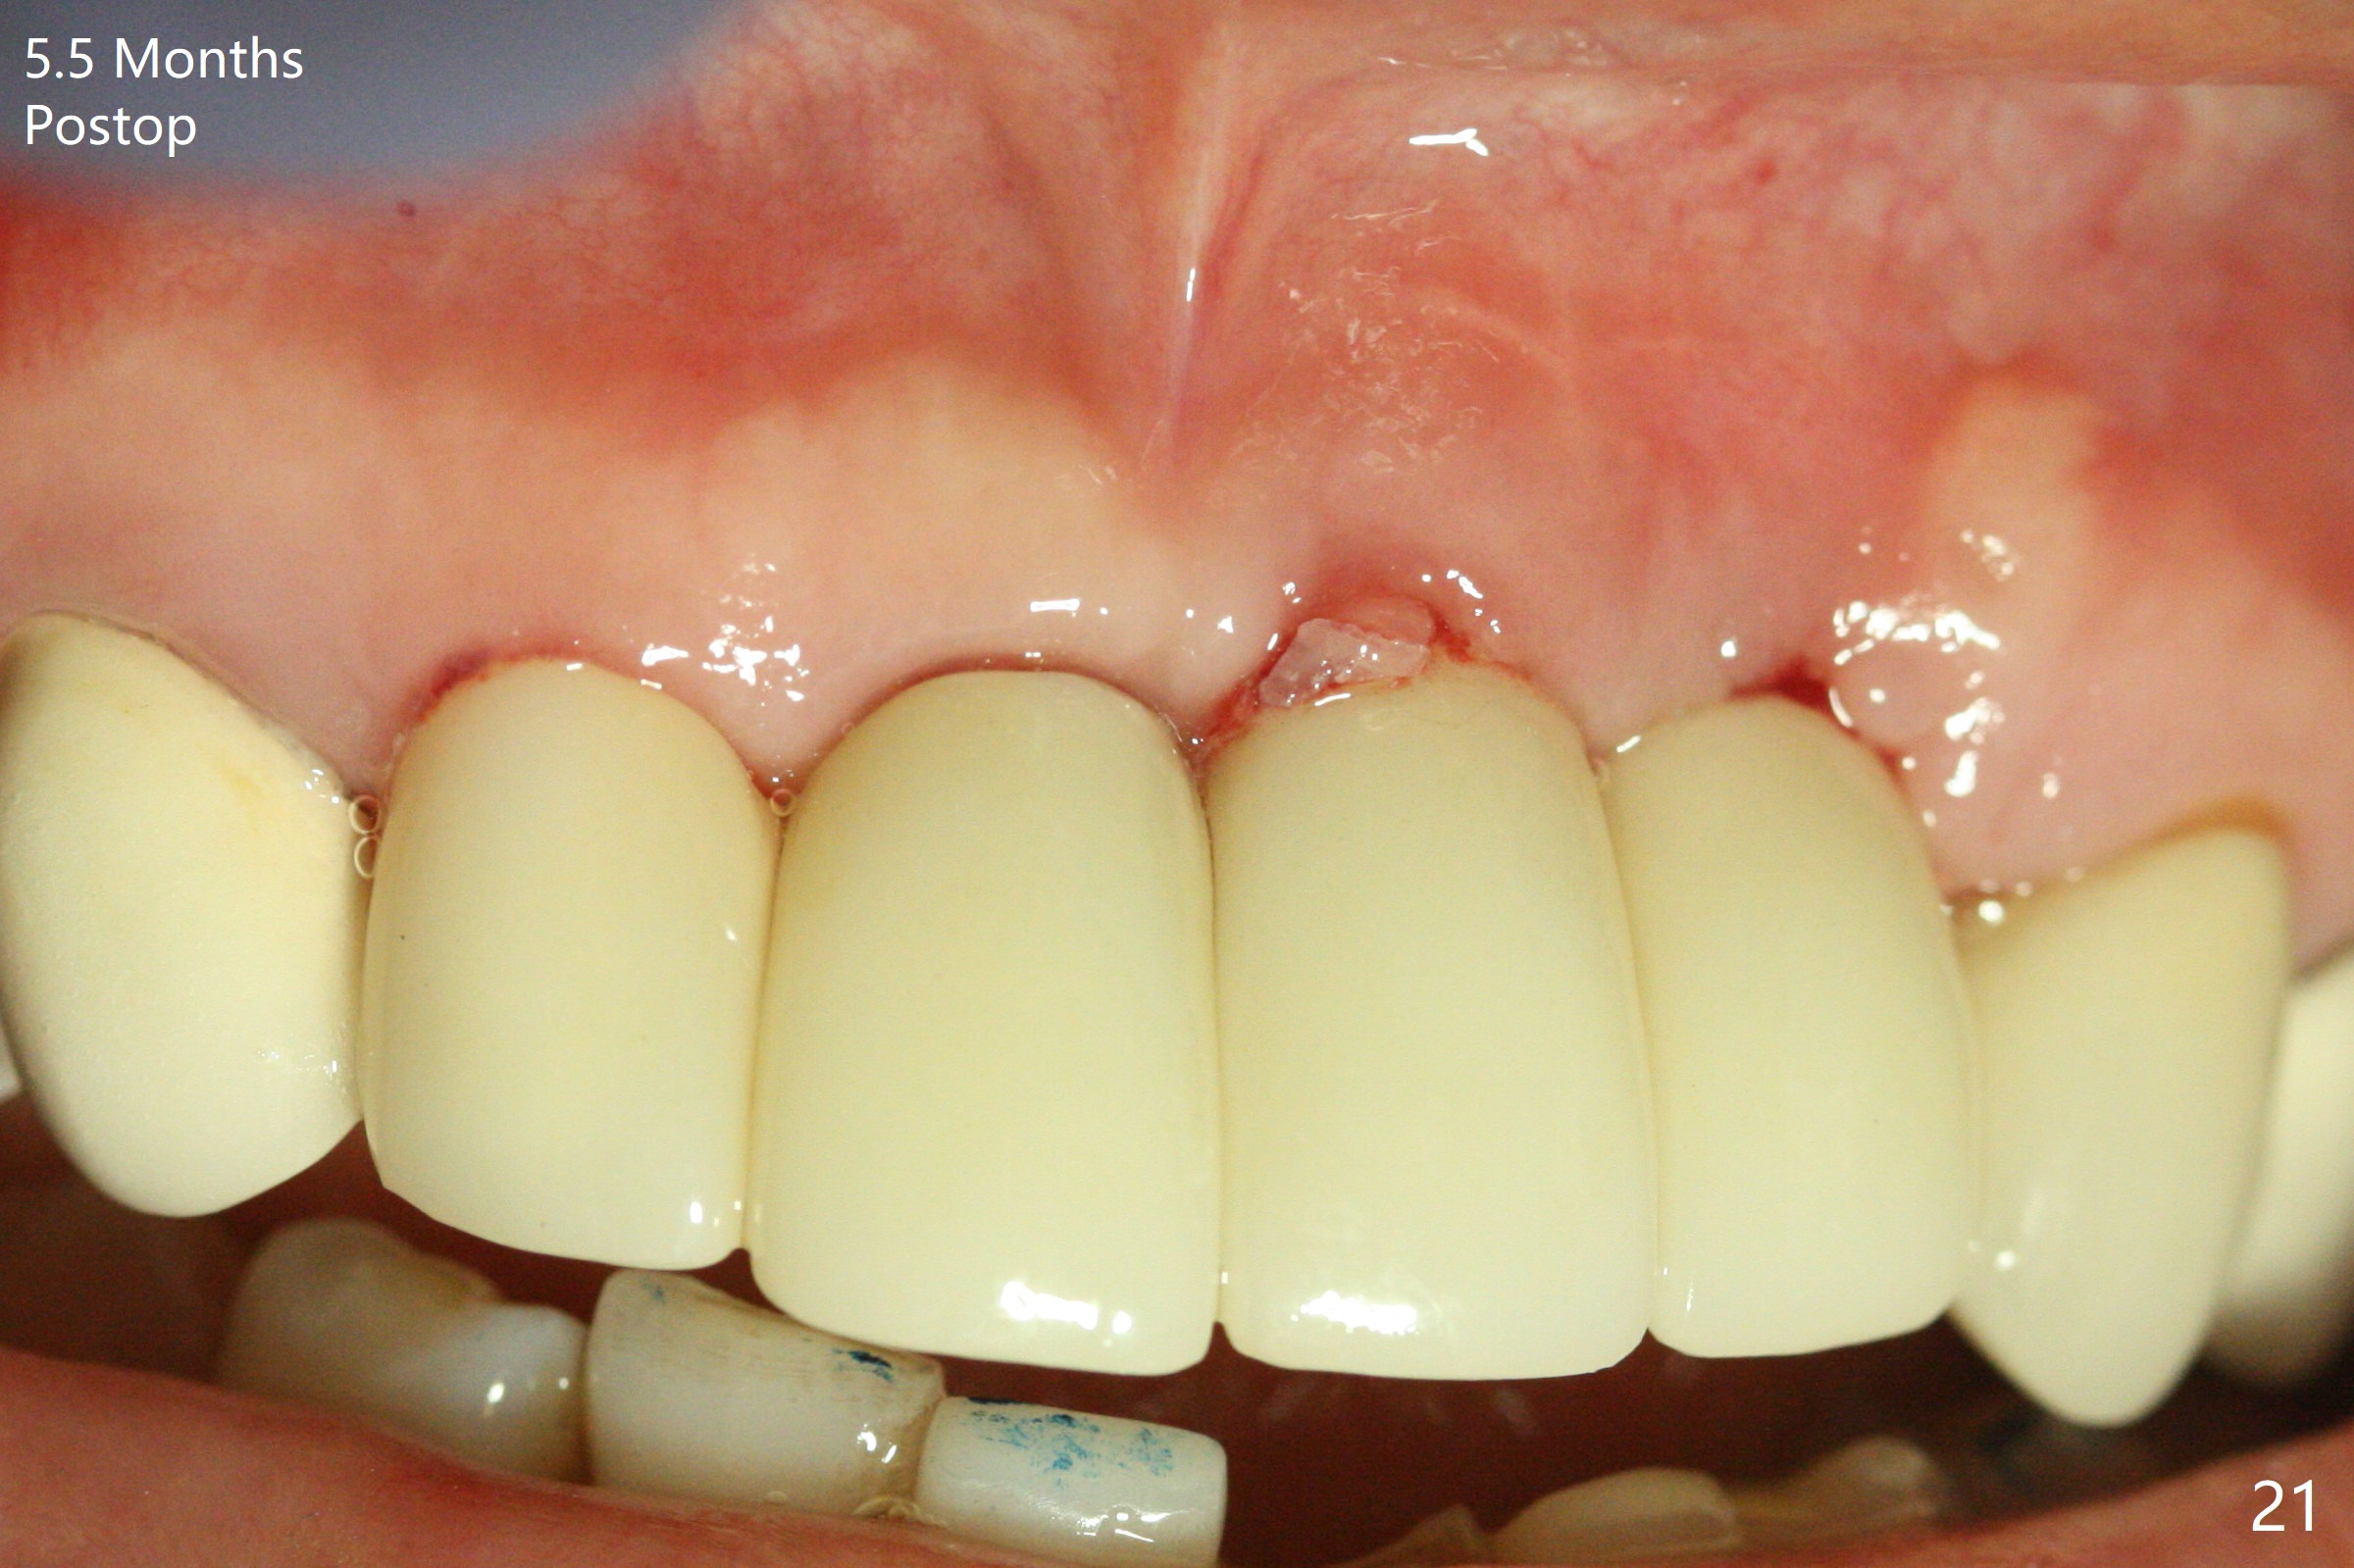

Incision shows exposure of microthreads at #9 and major threads at #10 due to buccal placement (Fig.1). There is bone palatal to the implant at #10 (Fig.2 P), to which a new implant will move. After implant removal, a narrower 1-piece implant (2.5x14(4) mm) is placed palatally at #10 (Fig.3,4) in combination of guide and free hand. At the site of #9 after implant removal, the guide is not used; a 3x17 mm angled 1-piece implant is placed with bad trajectory (Fig.5,6). After re-adjustment (Fig.7), the implant is placed at the right orientation (Fig.8). It appears that the guide is helpful. Allograft is placed mainly buccally (Fig.9,10 *), followed by a piece of collagen membrane (Fig.11). After tension release, flaps are approximated (Fig.12). The buccal gingiva at #9 and 10 recede nearly 2 months postop (Fig.13). Less recession at #9 is associated with more inflammation (Fig.14). The margin of the provisional is adjusted for gingival margin down growth and easy self cleaning with Water Pik (Fig.15). One month later, the gingival inflammation reduces, while there is no obvious buccal collapse (Fig.16,17). Impression is taken after laser gingivectomy nearly 4 months postop (Fig.18). While the gingiva around the implant at #9 is inflamed (periimplantitis?), the gingival cuff at #10 is well formed 5.5 months postop immediately before cementation (Fig.19). The buccal concavity at #10 is minimal (Fig.20). The gingival inflammation at #9 will be hopefully resolved after cementation of the final restorations (Fig.21). There appears to be new bone formation around the coronal implant threads 5.5 months postop (immediately post cementation, Fig.22). The microthreads at #9 may be not covered by the bone, the reason for the gingival erythema. The redness at #10 is asymptomatic 5.5 months post cementation (Fig.23). 粘固后两年牙槽嵴骨质并没有再生(图二十四),说明第一术中植体必须植入骨下(基台部分要长,否则难于修复),第二牙槽嵴处不应该有压力,植入2.5毫米植体,最后钻头应该是2.5毫米,骨下1-3毫米(尝试项目)。